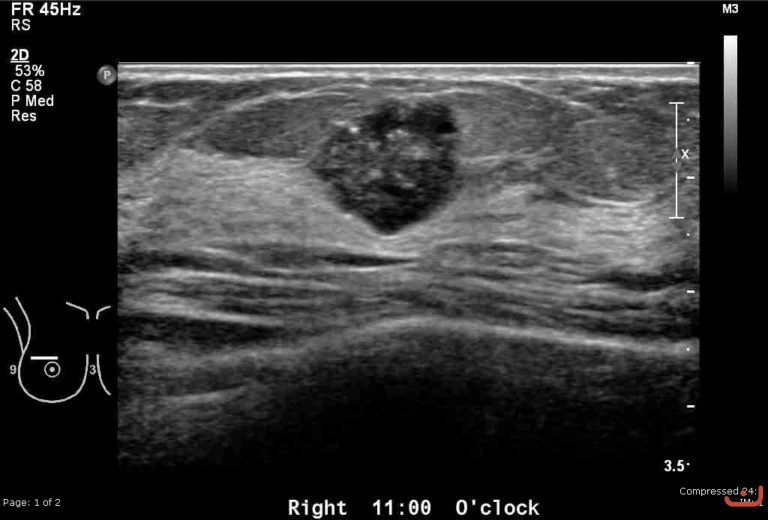

Malignant solid mass

Date

Thursday, 30 April 2015

166.75 KB (768 x 520 px)